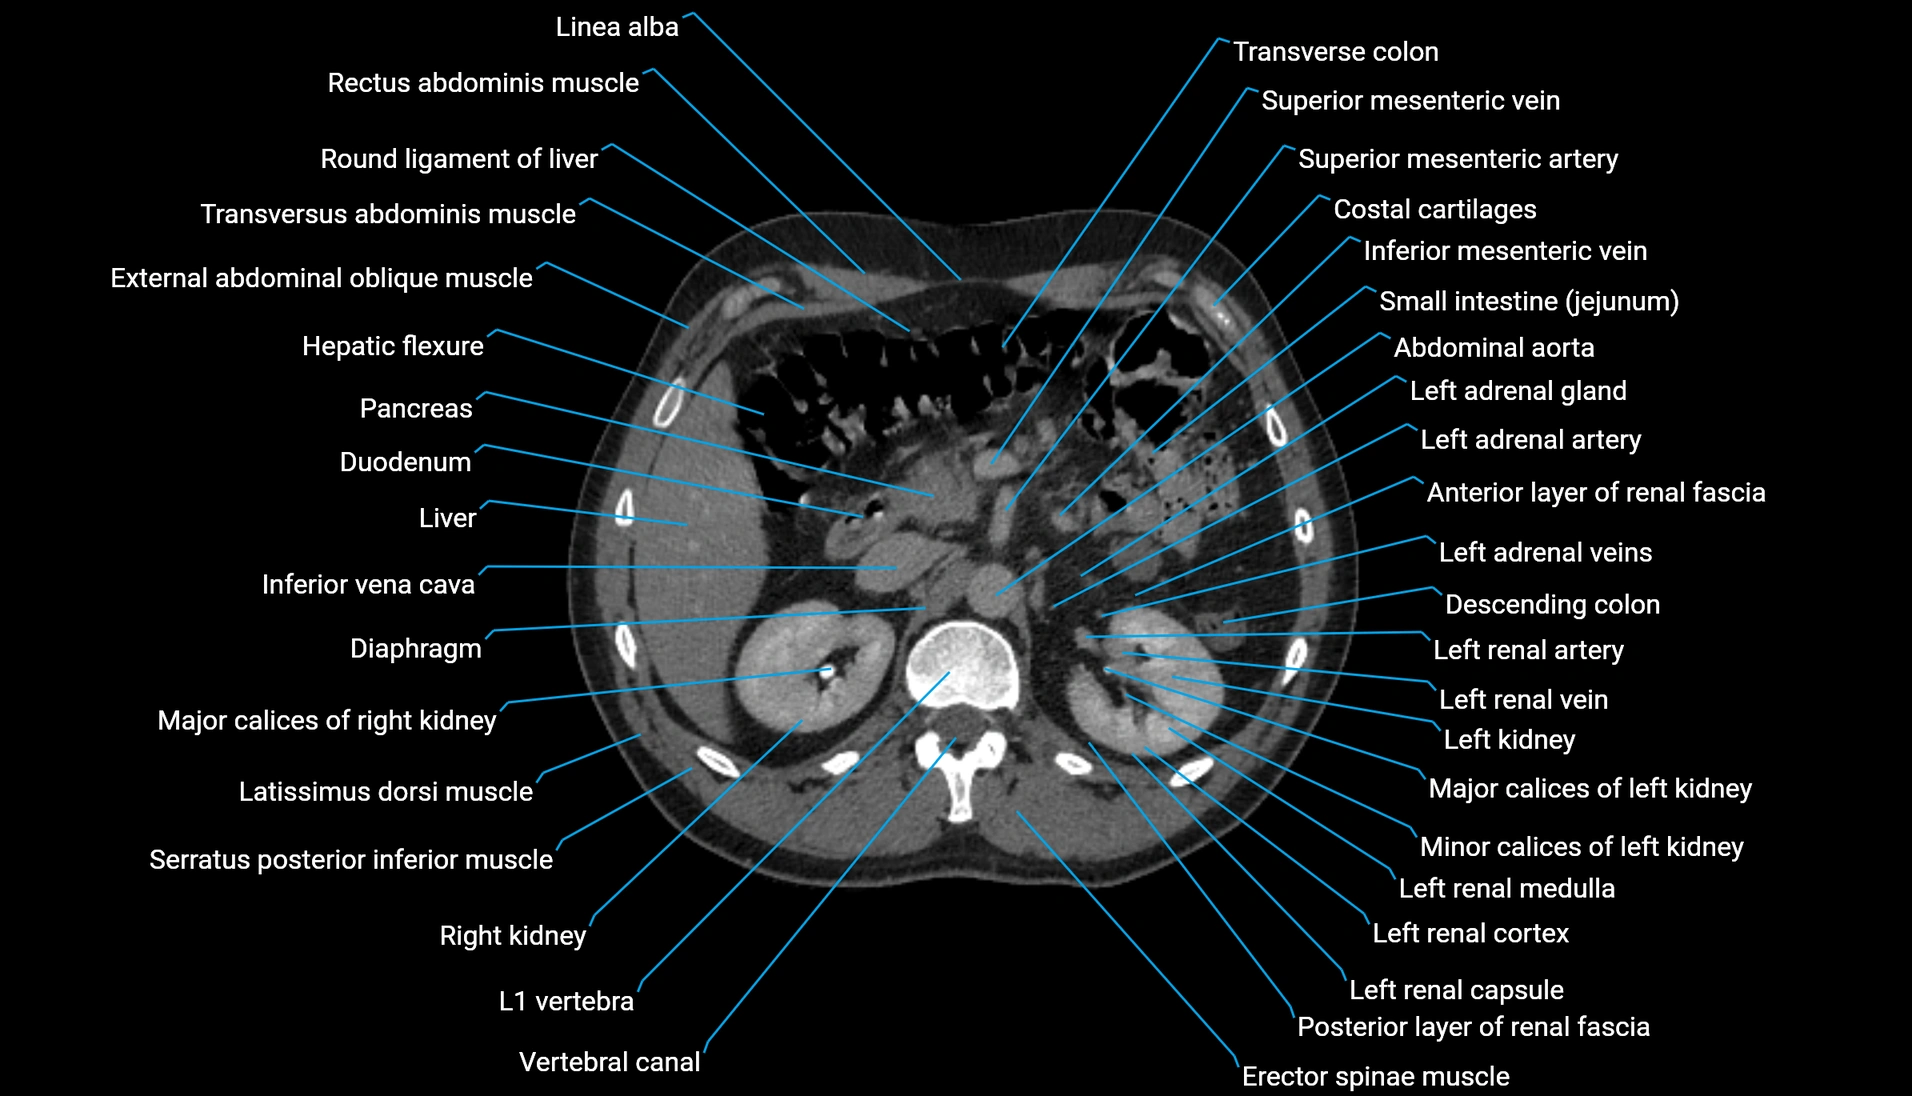

CT Appearance

Non-contrast CT:

-

Demonstrates cortical bone of acetabular rim in excellent detail

Detects fractures, dysplasia, retroversion, or bony overcoverage (pincer impingement)

3D reconstructions used in preoperative hip surgery planning

CT VRT 3D image

CT image